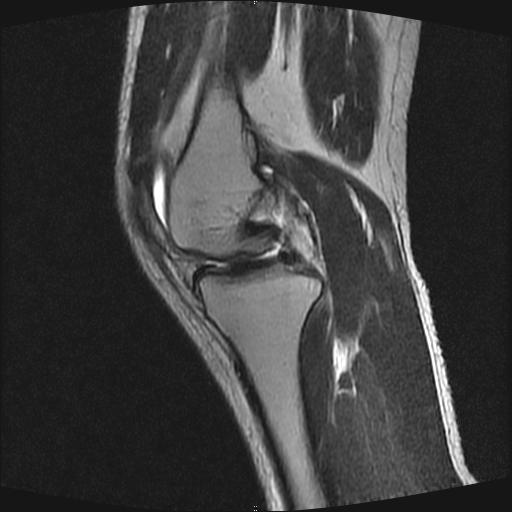

40岁男性,右膝关节外伤,x光平片示,髁间隆突撕脱骨折。

1、前交叉韧带撕裂;

2、外侧半月板后角撕裂;

3、关节腔积液。

前交叉韧带撕裂,关节腔积液.

半月板1-2级损伤   前交叉韧带撕裂伤   关节腔少量积液  诸骨未见新鲜外伤性改变

前交叉韧带撕裂,关节腔积液,支持!

半月板1-2级损伤   前交叉韧带撕裂伤   关节腔少量积液

内侧副韧带撕裂及关节腔积液是肯定的,但是前交叉撕裂确定吗?会不会有容积效应的因素,因为前一张前交叉显示清楚,连续性良好,且较光滑。请问楼主有关节镜支持吗?我们医院也经常有这样的患者,但苦于没有关节镜,而无法对照、证实(除非完全断裂),出现了不同的诊断结果只能毫无意义的争论。